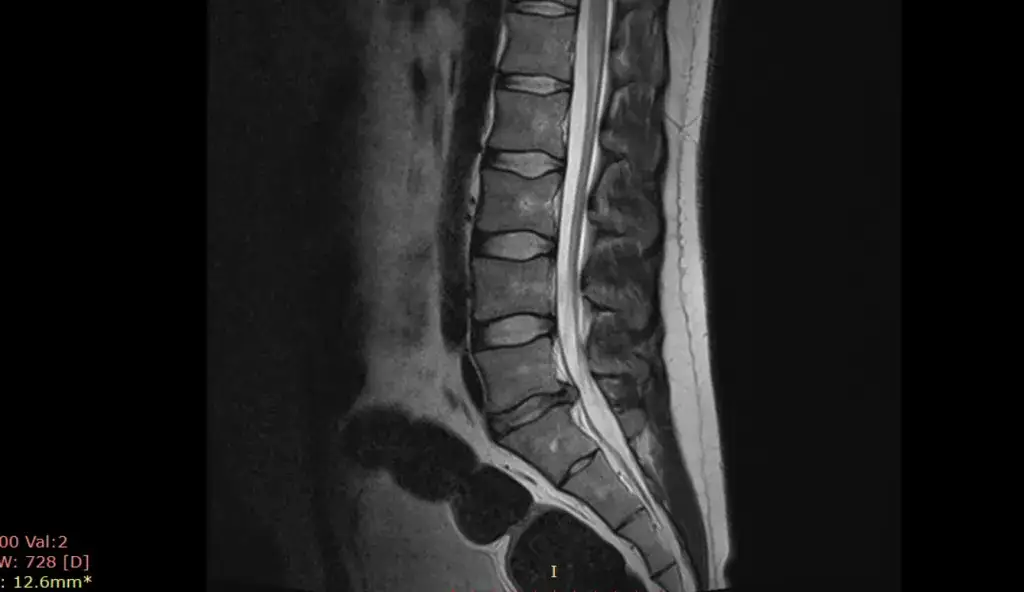

Czy przepuklina kręgosłupa może się cofnąć? Poznaj fakty o spontanicznej regresji, czynnikach wpływających na wchłanianie się przepukliny i roli rehabilitacji w procesie leczenia.

Poznaj skuteczne metody leczenia przepukliny jądra miażdżystego. Od terapii zachowawczej po zabiegi operacyjne - dowiedz się, jakie opcje są dostępne i która może być najlepsza dla Ciebie.